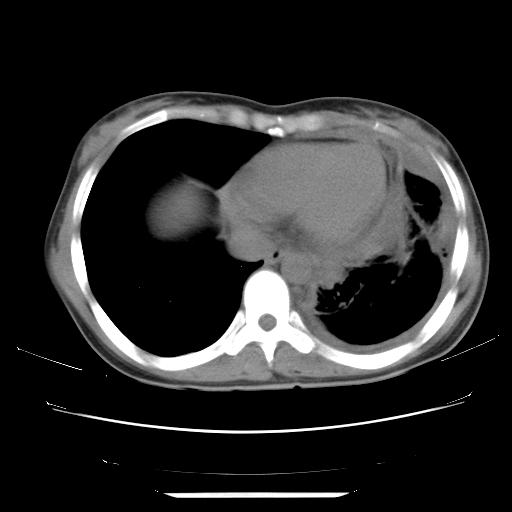

女,29岁,胸部不适,在外院胸片提示胸腔积液,到我院ct检查。

纵膈窗

左侧纵隔胸膜包裹性积液、左侧胸腔积液、胸膜肥厚粘莲,考虑结核性胸膜炎

左肺上叶不张,左侧胸水,叶间裂积液,纵隔淋巴结,脾脏钙化,考虑左肺上叶支气管内膜结核,结核性胸膜炎,脾结核

支持两肺继发性肺结核,左侧胸膜腔包裹性积液、胸膜肥厚,脾内多发钙化(结核钙化)。

左侧纵隔胸膜包裹性积液、左侧胸腔积液、胸膜肥厚粘莲,考虑结核性胸膜炎.左肺上叶支气管内膜结核,结核性胸膜炎,脾结核.

左肺上叶不张,左侧胸水,叶间裂积液,纵隔淋巴结,脾脏钙化,考虑左肺上叶支气管内膜结核,结核性胸膜炎,脾结核。支持!